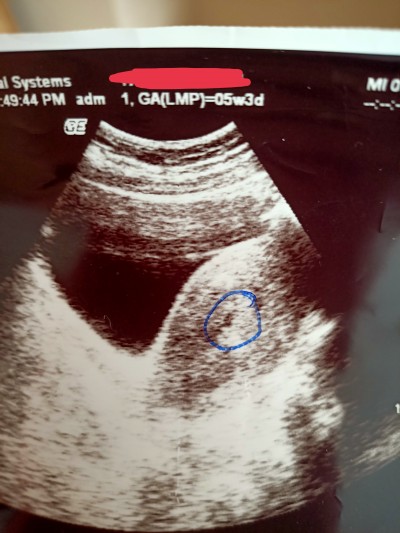

Kese görüntüsü ama dr emin olamadi

Gebelik haftası 5

Benim kesemi 446 ile görmüştü doktor 5+3 haftalık hamileydim son adet tarihime göre ultrasyonda da aynıydı zaten

Kesedenmi emin olamadi canım hamile olduğunda mı anlamadım kese var gbi duruyor ama minnacıkk

Gebelik var ama kese net değil dedi

Niye kör mü doktor kız gayet orda işte

Küçük dedi kese için bende anlamadım beta yavaş yukseliyor